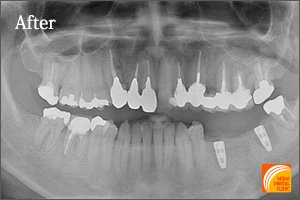

症例2

Before

期間 :3カ月

回数 :6回

費用 :766,800円

内容 :インプラント2本、外科用ステント、セラミック冠3本分含む

After

左下奥3本を失われた患者さんです。3本歯がないからといって3本インプラントが必要なわけではありません。2本インプラントを埋入することにより3本の歯を支えるインプラントブリッジにより治療しました。